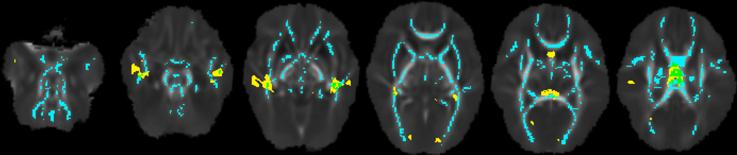

Structural images from 328 infants (91 VP, 63 MP, 104 LP and 70 FT) were segmented into white matter, cortical grey matter, cerebrospinal fluid (CSF), subcortical grey matter, brainstem and cerebellum. Global tissue volumes were analysed, and additionally, cortical grey matter and white matter volumes were analysed at the regional level using voxel-based morphometry. Fractional anisotropy (FA), mean diffusivity (MD), axial diffusivity (AD) and radial diffusivity (RD) images from 361 infants (92 VP, 69 MP, 120 LP and 80 FT) were analysed using Tract-Based Spatial Statistics. Statistical analyses involved examining the overall effect of GA group on global volumes (using linear regressions) and regional volumes and microstructure (using non-parametric permutation testing), as well performing post-hoc comparisons between the GA sub-groups.

On global analysis, cerebrospinal fluid (CSF) volume was larger in all preterm sub-groups compared with the FT group. On regional analysis, volume was smaller in parts of the temporal cortical grey matter, and parts of the temporal white matter and corpus callosum, in all preterm sub-groups compared with the FT group. FA was lower, and RD and MD were higher in voxels located in much of the white matter in all preterm sub-groups compared with the FT group. The anatomical locations of group differences were similar for each preterm vs. FT comparison, but the magnitude and spatial extent of group differences was largest for the VP, followed by the MP, and then the LP comparison. Comparing within the preterm groups, the VP sub-group had smaller frontal and temporal grey and white matter volume, and lower FA and higher MD and RD within voxels in the approximate location of the corpus callosum compared with the MP sub-group. There were few volume and microstructural differences between the MP and LP sub-groups.

All preterm sub-groups had atypical brain volume and microstructure at TEA when compared with a FT group, particularly for the CSF, temporal grey and white matter, and corpus callosum. In general, the groups followed a gradient, where the differences were most pronounced for the VP group, less pronounced for the MP group, and least pronounced for the LP group. The VP sub-group was particularly vulnerable compared with the MP and LP sub-groups.